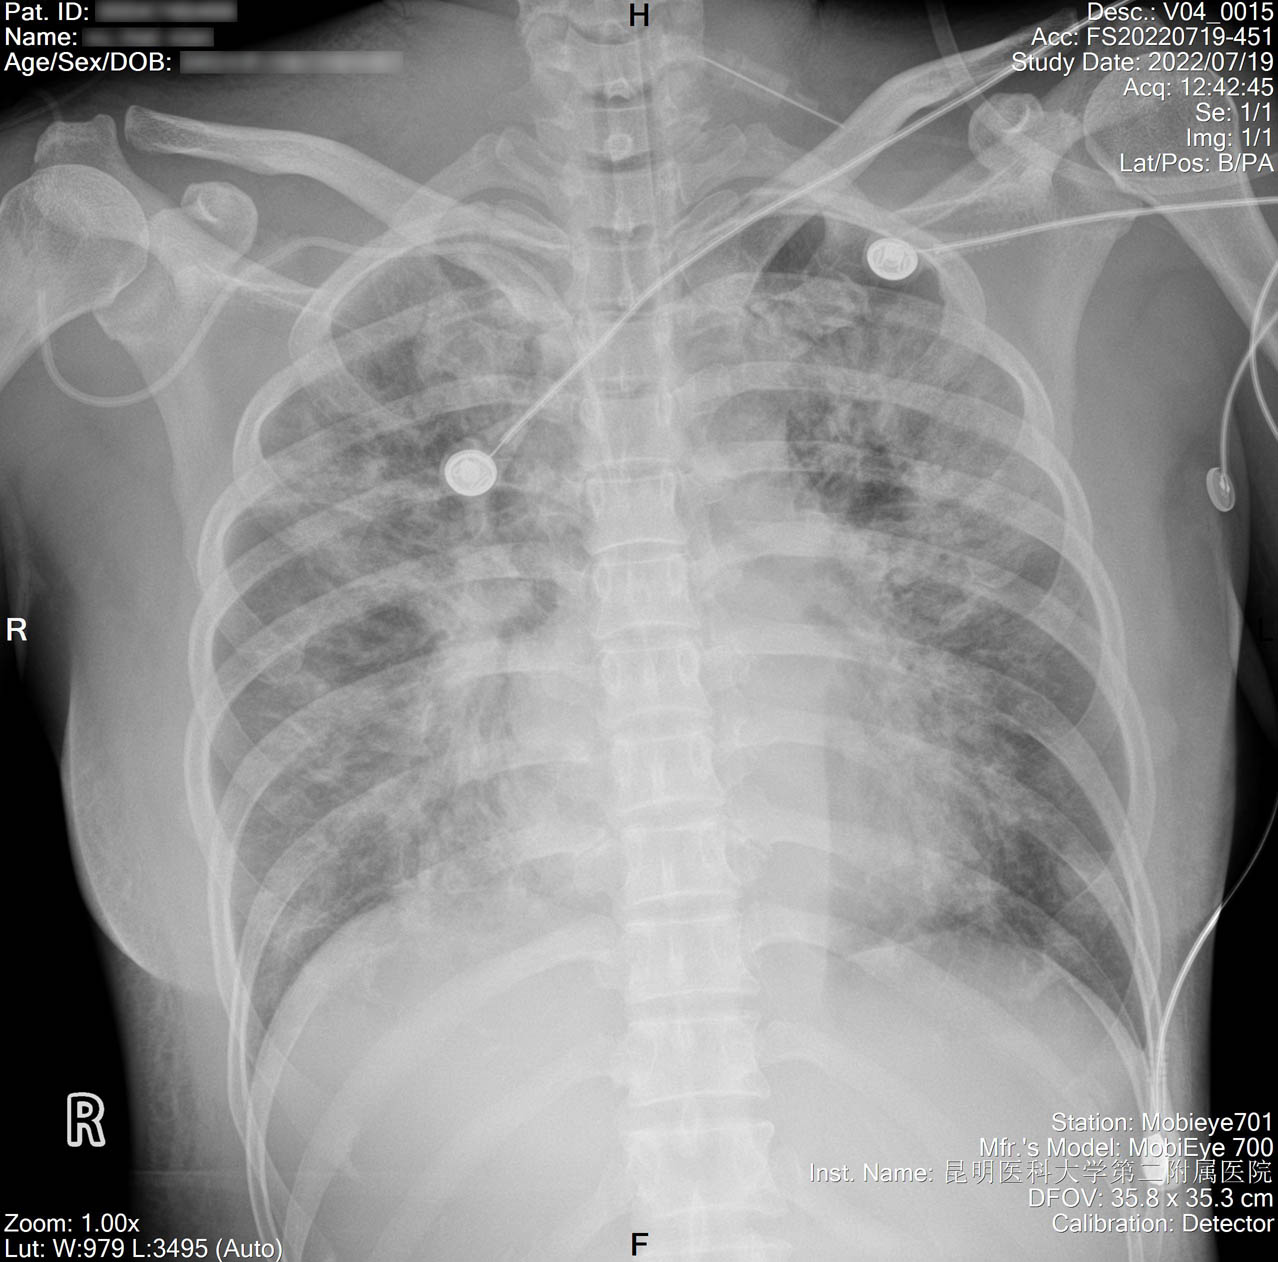

2022-07-18_胸片